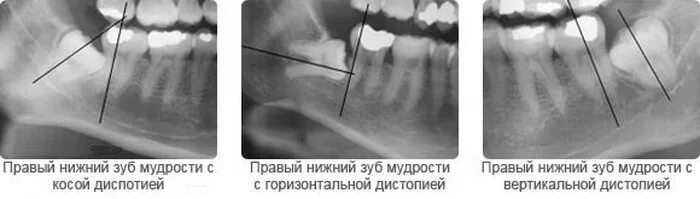

Удалить зубы семерки